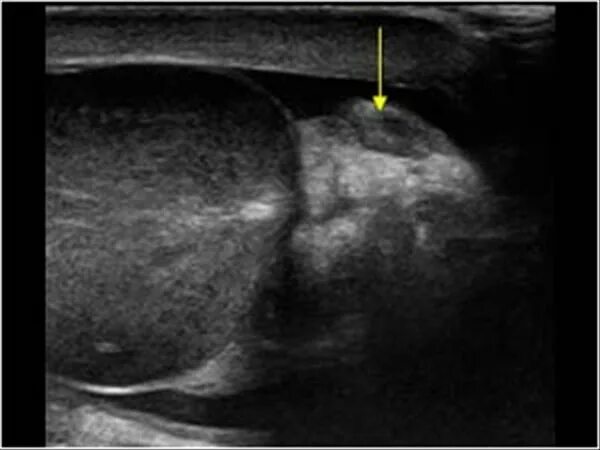

Обеих яичек